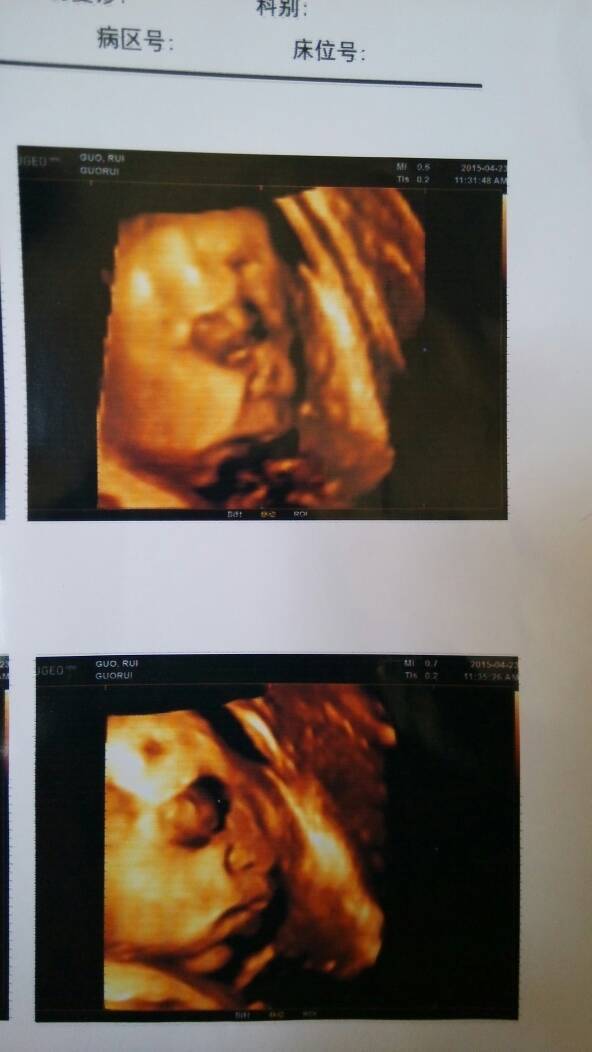

孕36周 去做了个四维 宝的照片,丑不拉几的 孕36周 去做了个四维 宝的照片,丑不拉几的😭😭😭😍😍😍😍 点击展开 屋顶星星93 2015-04-24 17:22 为您推荐: 其他回答 没事,生出来长开了就漂亮了。 开心的糖果 2015-04-24 22:03 !!!!!! 暖心程硕滴麻麻。 2015-04-24 18:27 幸福吧。。 小禹厚的妈妈 2015-04-24 17:45 你看你那表情。。。。😱 ぐHappinessゞ 2015-04-24 17:44 呵呵,生下来就爱不释手了 小禹厚的妈妈 2015-04-24 17:39 加载更多 相关问题 为什么我四维彩超任出来和我的孕周一样可昨天做了彩超是孕32周呢 孕七个月做四维医生说宝宝偏小两周,只有三斤,是什么原因呢?好担心 请问一下各位宝妈,一般孕几周做四维呢?想提前预约